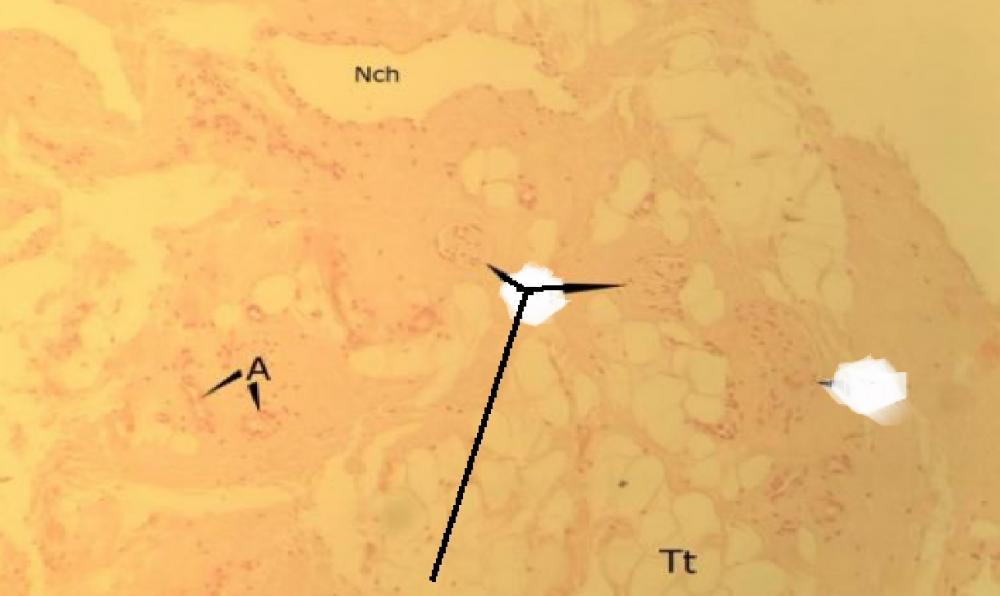

Pytanie 629

pęcherzyk wypełniony koloidem (przysadka mózgowa - część gruczołowa, barwienie metodą Sliddersa).jpg